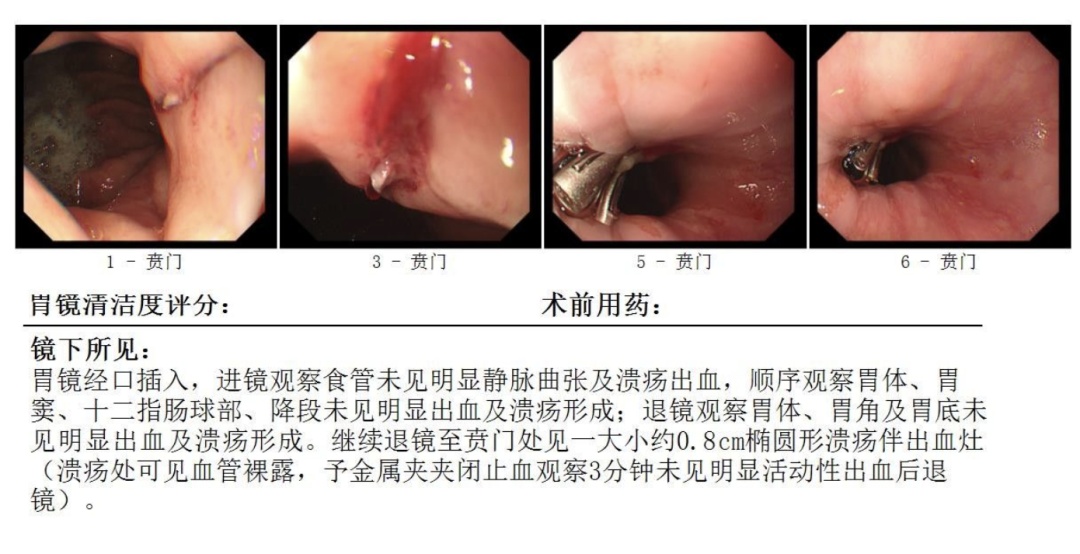

中午时分,在全麻状态下,消化内科团队为张师傅完成了急诊胃镜。检查发现,出血点位于食管-贲门连接处,确诊为贲门黏膜撕裂(Mallory-Weiss综合征)伴活动性出血。这种撕裂往往由剧烈呕吐或干呕引发,而张师傅长期大量饮酒导致的胃黏膜脆弱,正是此次大出血的“导火索”。

发现出血点

止血后

内镜下止血随即展开,出血被成功控制。术后,患者生命体征趋于平稳,意识清醒,当天下午转入消化科病房继续观察治疗。